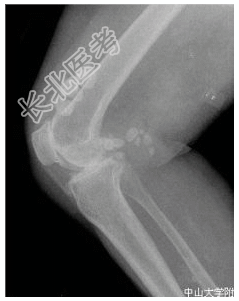

- [材料题] 患者女,55岁,双膝隐痛十余年。查体:双膝压痛,局部软组织肿胀,触之硬物感。行双膝关节正侧位片检查。

- 简答题1、患者的诊断及依据是什么?

- 简答题2、鉴别诊断是什么?